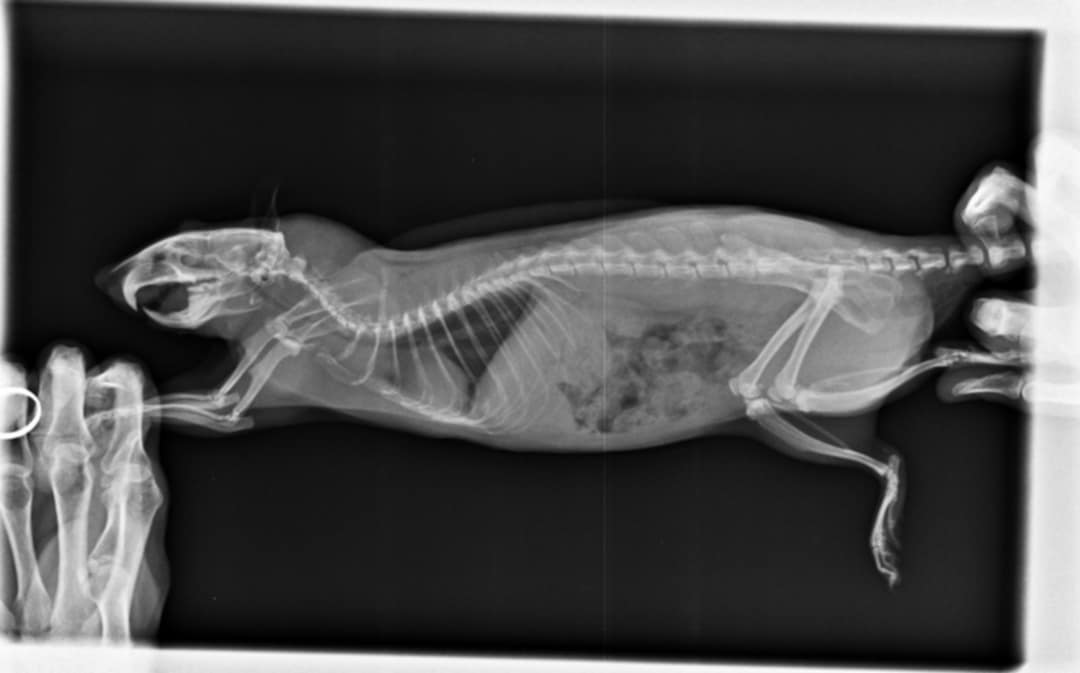

Je mets les radios, Mathilde n'arrive pas à les charger:

Radio du 5 mai:

Les radios sont pas terribles, pas très bien exposées ni assez centrées sur la cage thoracique et floues, du coup perso j'arrive pas à voir grand chose >< Mais bon tes vétos ont sans doute davantage l'habitude. Par contre je trouve aussi que le cœur est gros.